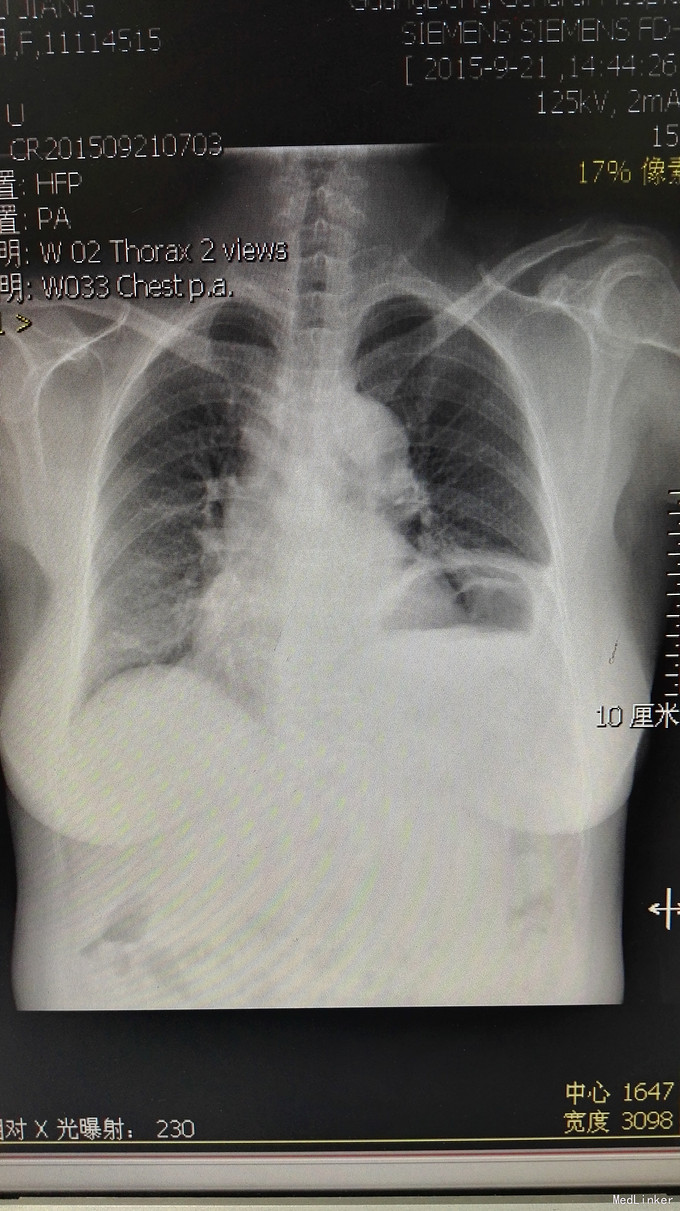

患者老年女性,因“反复咳嗽、气促4年余,再发20余天”入住本科。患者有支气管哮喘病史,本次发作治疗过程中,发现左侧横膈抬高。

查体:胸廓无畸形,双肺闻及较多干、湿罗音,双侧呼吸运动基本对称,幅度稍有减少,心腹体查未见异常,双下肢无水肿。 辅助检查:外院胃镜:慢性萎缩性胃炎。CT:左侧横膈抬高,未见报告。X线如图

诊断:1、支气管哮喘急性发作2、左侧横膈抬高查因 治疗上,主要针对支气管哮喘,抗炎、平喘、止咳、化痰及对症治疗。完善膈肌B超、颈椎MR、胸透等相关检查,明确左侧横膈抬高原因。

常见的一侧膈肌抬高的原因有哪些?补充一点,本例阅CT片未发现纵膈、心脏、胃部病变。